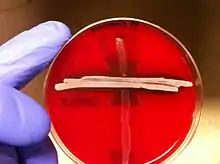

CAMP

A CAMP test is used to differentiate between Streptococcus agalactiae and other species of beta-hemolytic Streptococcus. This biochemical test uses the fact that Streptococcus agalactiae excretes a CAMP substance, making it slightly more hemolytic, which can be observed on blood agar media.[21]

Reverse CAMP

The reverse CAMP test utilizes the synergetic hemolytic abilities of the CAMP factor produced by Streptococcus agalactiae with the α-toxin produced by Clostridium perfringens. Streaking these two organisms perpendicular to each other on a blood agar plate will yield a “bow-tie” clearing of the blood agar by the hemolytic capabilities of the two organisms’ toxins. Incubation requires 24 hours at 37 °C.[34]